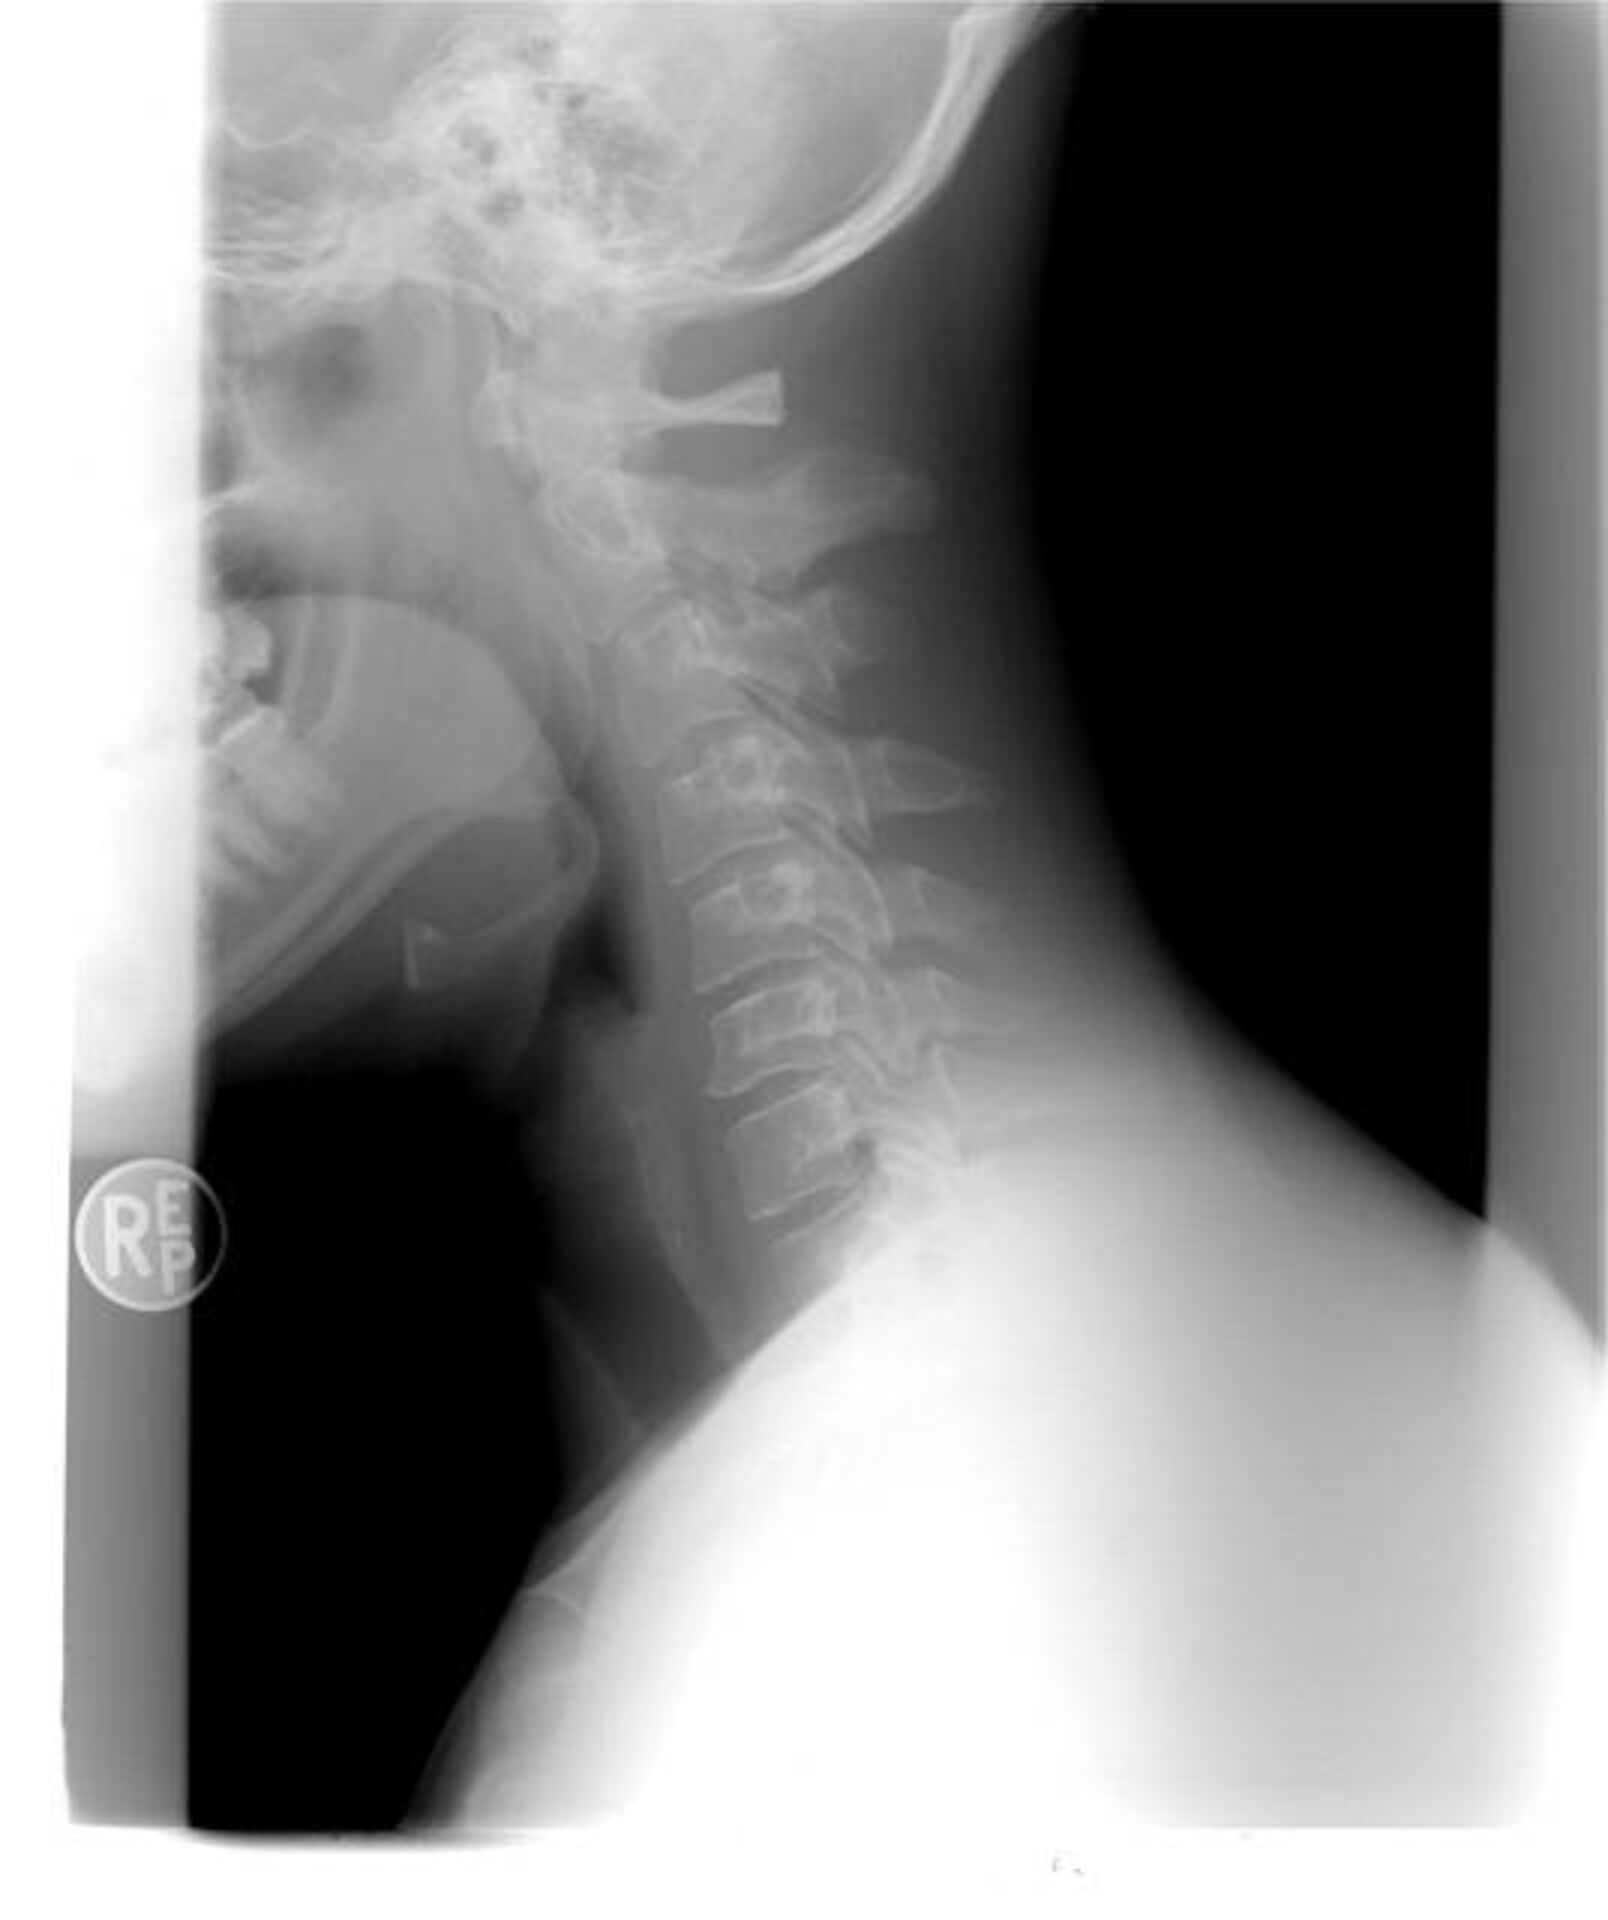

3. 15 037 € de dommages intérêts alloués à une victime d’accident de la route conducteur de voiture, ayant subi une entorse cervicale à Marseille.

15 037 € de dommages intérêts alloués à une victime d’accident de la route conducteur de voiture, ayant subi une entorse cervicale à Marseille.

Le conducteur de voiture victime d'accident d'accident de la route à Marseille ayant subi une entorse cervicale a droit à l'indemnisation de son dommage corporel, sur le fondement de la loi du 5 juillet 1985, dès lors qu'il n'a pas commis de faute de conduite.

Notre cabinet d’avocat a obtenu récemment la somme de 15 037 € à titre d’indemnisation du dommage corporel d’une victime d’accident de la route à Marseille, ayant subi une entorse cervicale.